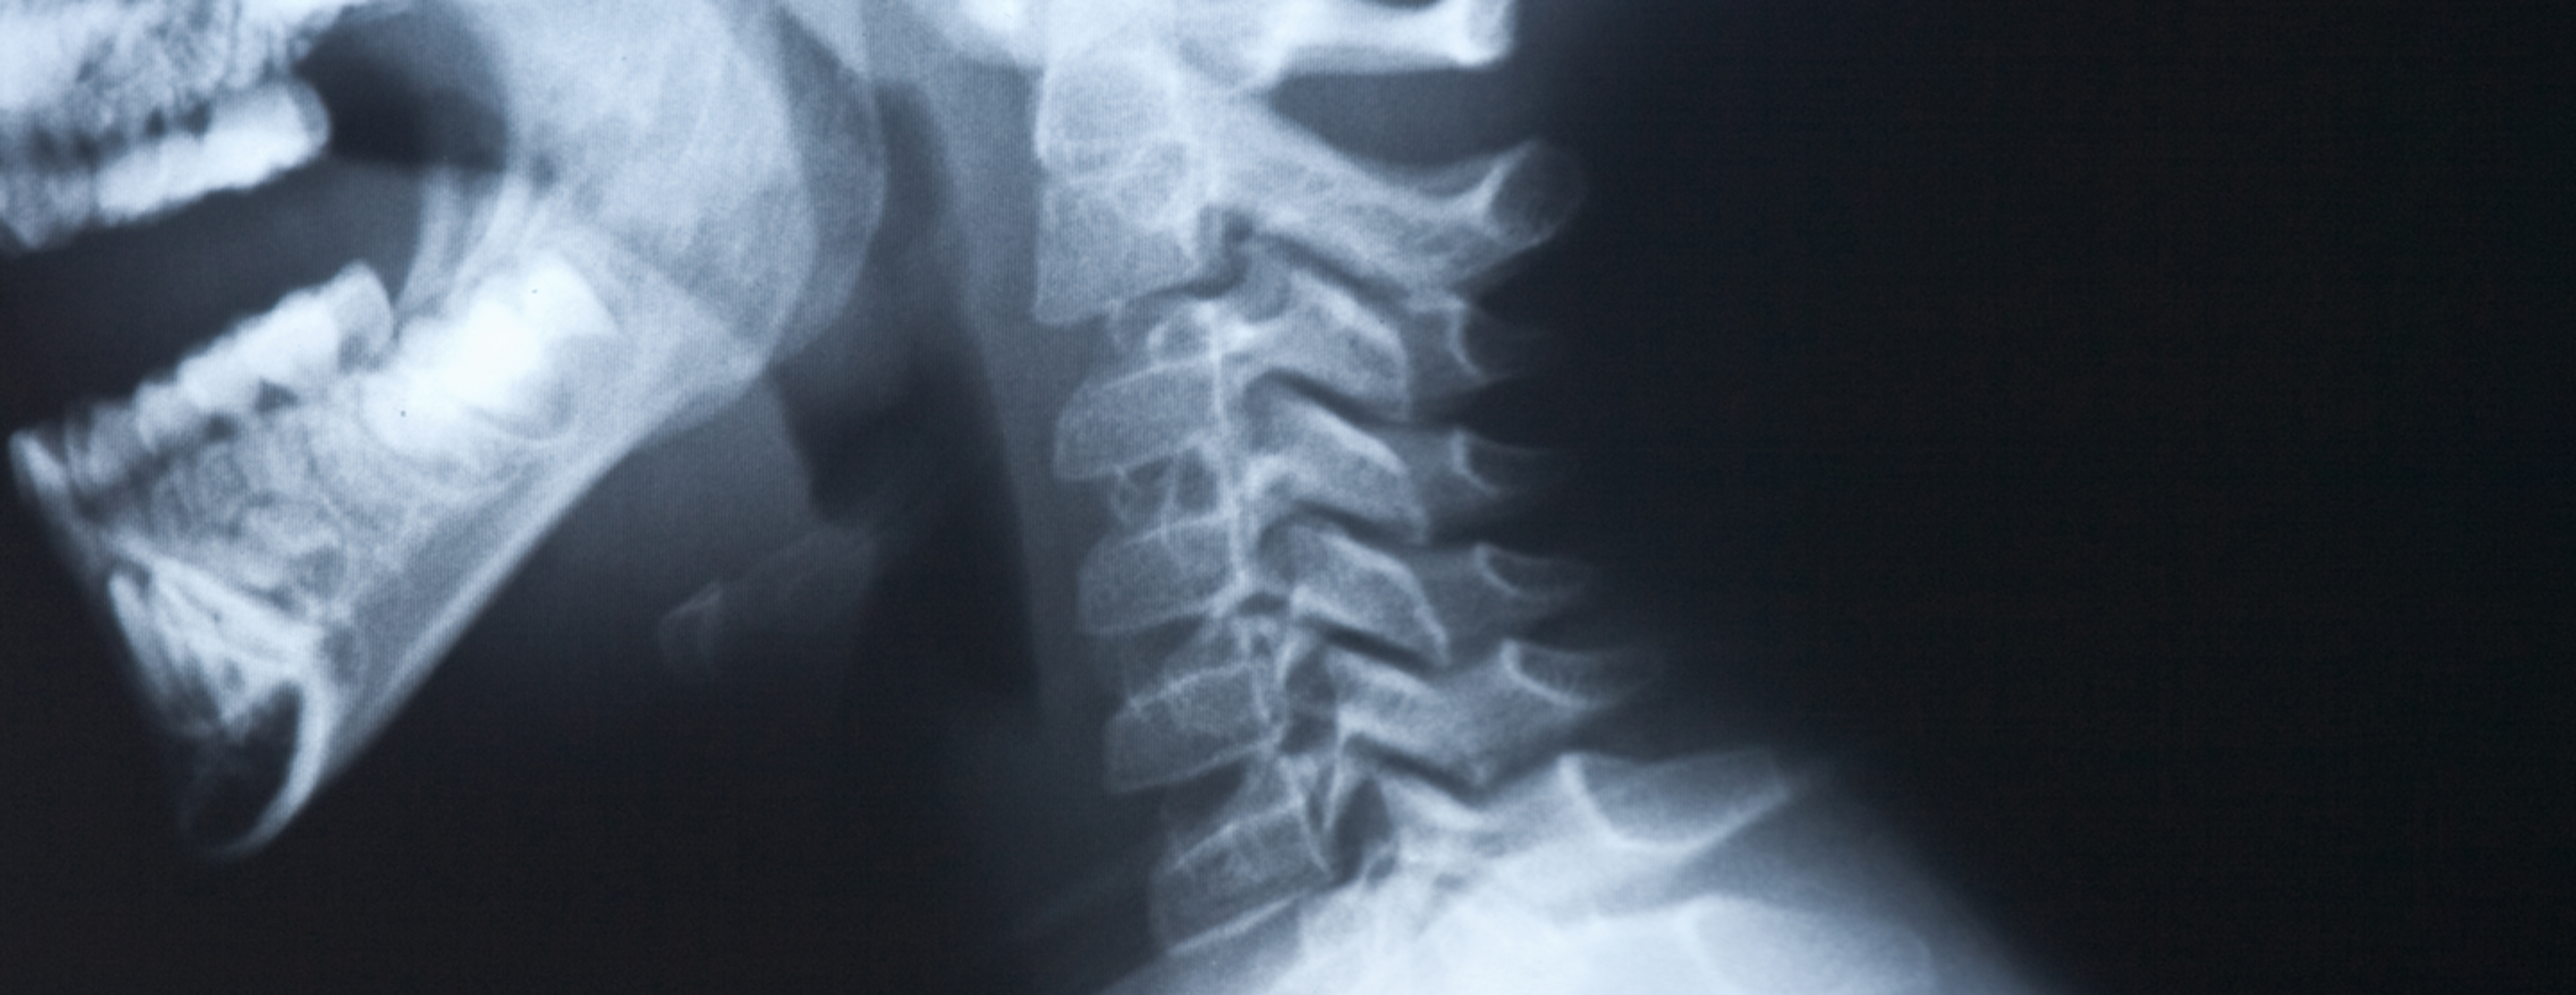

Neck x-ray

A neck x-ray is an imaging test to look at the cervical vertebrae. These are the 7 bones of the spine in the neck.

X-ray - neck; Cervical spine x-ray; Lateral neck x-ray